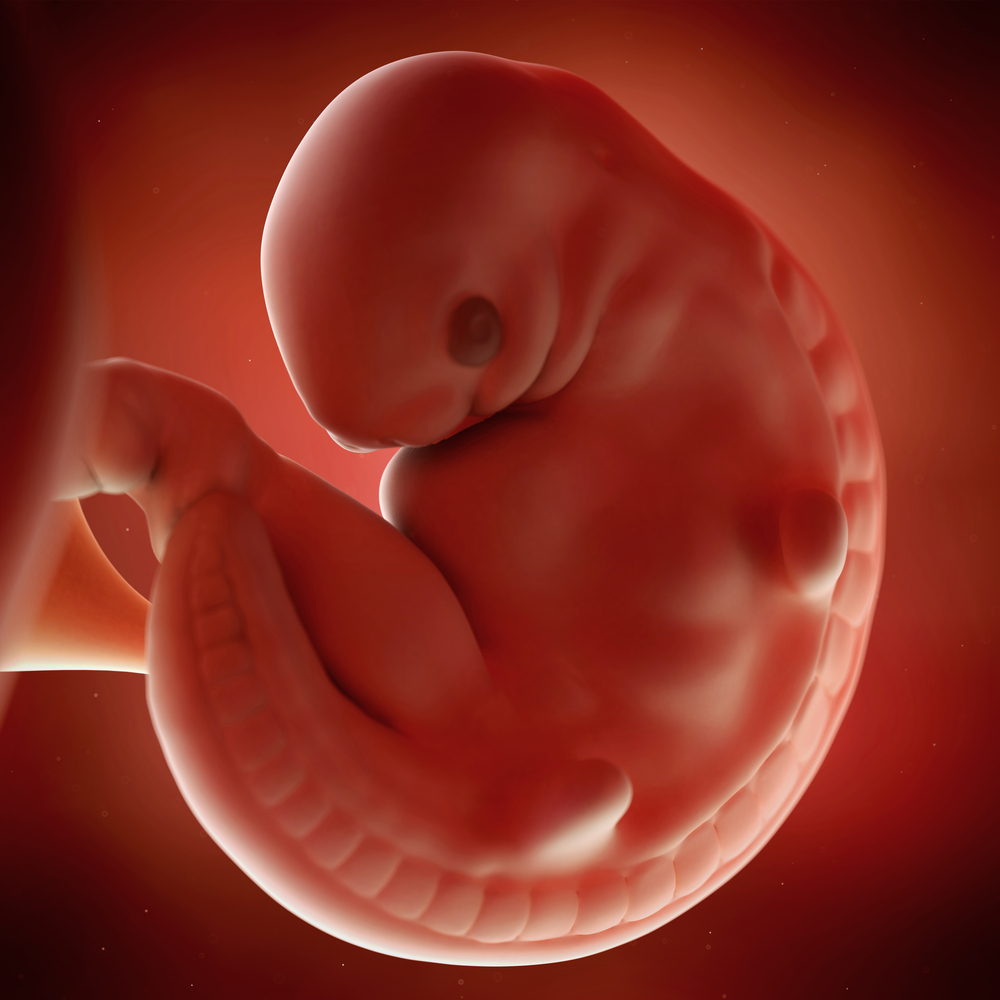

At six weeks, your baby is about ⅛ or ¼ inches long and looks something like a tadpole.

At 6 weeks, about 2 weeks after you confirm your pregnancy, your baby is just the size of a pea or a grain of rice. By this time, the baby develops a heartbeat, and the limb buds appear. Facial features and organs begin forming around this time.